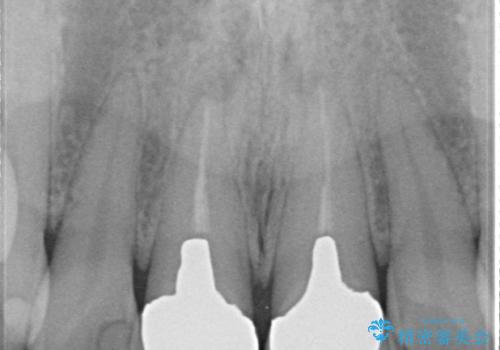

- 10年前ほどに前歯に装着されたセラミックの根元の方が黒くなってきたのが気になるとのことで来院されました。

上顎の前歯の歯茎が下がり、ご自身の歯が露出している状態でした。

金属の土台をファイバーコアに交換後、オールセラミッククラウンを装着する計画としました。